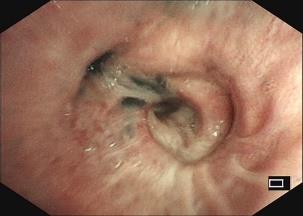

• 获得性免疫缺陷综合征合并马尔尼菲篮状菌导致肠道感染的内镜下表现(附6例报告)

摘要:目的 探讨获得性免疫缺陷综合征(AIDS)合并马尔尼菲篮状菌(TM)感染导致肠道感染的内镜下特征。方法 回顾性分析2022年11月-2024年10月于该院确诊为AIDS合并TM感染导致肠道感染的6例患者的临床资料。包括:临床症状、实验室检查、影像学检查、内镜检查和病理检查等。结果 6例患者中,男5例,女1例;发病年龄26~67岁;AIDS合并TM感染导致肠道感染患者的临床表现为:腹泻、腹痛、腹胀和恶心呕吐。其中,2例有消化道出血表现。实验室检查:6例患者外周血白细胞计数为(1.37~4.49)×109/L,血红蛋白计数为(67~99)g/L;CD4+T淋巴细胞为(1~52)个/μL,CD8+ T淋巴细胞为(61~321)个/μL,CD4+T淋巴细胞/CD8+T淋巴细胞比值为(0.01~0.18)。6例患者均行HIV RNA检测。其中,5例HIV RNA阳性。血培养:可见丝状真菌,报告显示为TM。影像学检查:6例患者CT结果可见肠系膜及腹膜后多发淋巴结肿大。内镜检查:6例患者内镜下均可见肠道病变。其中,十二指肠糜烂溃疡2例,结肠多发糜烂溃疡4例。病理检查:6例患者幽门螺杆菌(Hp)结果均为阴性,黏膜下可见成簇的小球形真菌孢子,符合TM感染;特殊染色:PAS(+),六胺银染色(+)。结论 当AIDS晚期患者出现消化道症状时,应警惕TM感染,病变部位常见于全结肠和直肠,亦可累及十二指肠,内镜下表现多为溃疡、糜烂和隆起性病变,形态表现无特异性;及时行胃肠镜检查、病理活检、特殊染色和免疫组化是确诊的关键。